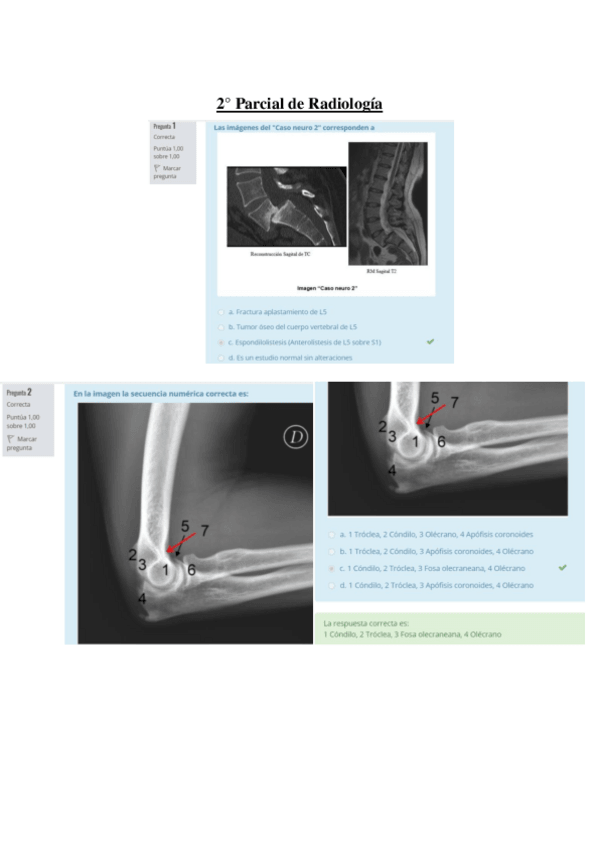

2º Parcial radio

He publicado nuevos apuntes de 2º Radiologia General: 2º Parcial radio